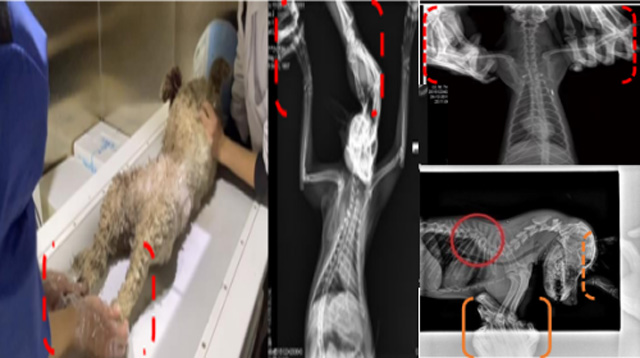

現(xiàn)在寵物醫(yī)療設備得到高速發(fā)展,現(xiàn)在有越來越多的寵物診療機構配置X射線裝置如寵物DR。寵物骨折或者有其他疾病不能通過直觀看出來的。寵物診所醫(yī)生都會使用寵物DR來做輔助檢查。但是有時候寵物醫(yī)生沒有加強防護,就在寵物DR室給寵物拍X片做檢查。這樣也是會受到X射線的輻射。因為X射線上崗是屬于職業(yè)病危害崗位。長期的輻射會對人體造成一定的危害。寵物醫(yī)生也需要接受X射線照射的上崗前都必須進行放射工作人員的職業(yè)健康體檢。體檢不合格的話是不能擔任放射工作的。未經(jīng)上崗前職業(yè)健康體檢的勞動者從事接觸職業(yè)病危害作業(yè)的行為,已經(jīng)違反了《中華人民共和國職業(yè)病防治法》第三十五條規(guī)定,依據(jù)《中華人民共和國職業(yè)病防治法》第七十五條規(guī)定,需要進行整改罰款。開展寵物放射診療活動,在日常工作中,對本機構的X射線危害的職業(yè)病防治,需要知道并做到以下內(nèi)容: